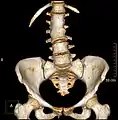

Lumbarization of sacral vertebra 1, seen as 6 vertebrae that do not connect to ribs.

Lumbarization is an anomaly in the spine. It is defined by the nonfusion of the first and second segments of the sacrum. The lumbar spine subsequently appears to have six vertebrae or segments, not five. This sixth lumbar vertebra is known as a transitional vertebra. Conversely the sacrum appears to have only four segments instead of its designated five segments. Lumbosacral transitional vertebrae consist of the process of the last lumbar vertebra fusing with the first sacral segment. [1] While only around 10 percent of adults have a spinal abnormality due to genetics, a sixth lumbar vertebra is one of the more common abnormalities. [2]

Sacralization of the L5 vertebra is seen at the lower right of the image.

Sacralization of the fifth lumbar vertebra (or sacralization) is a congenital anomaly, in which the transverse process of the last lumbar vertebra (L5) fuses to the sacrum on one side or both, or to ilium, or both. These anomalies are observed in about 3.5 percent of people, and it is usually bilateral but can be unilateral or incomplete (ipsilateral or contralateral rudimentary facets) as well. Although sacralization may be a cause of low back pain, it is asymptomatic in many cases (especially bilateral type). Low back pain in these cases most likely occurs due to biomechanics. In sacralization, the L5-S1 intervertebral disc may be thin and narrow. This abnormality is found by X-ray.